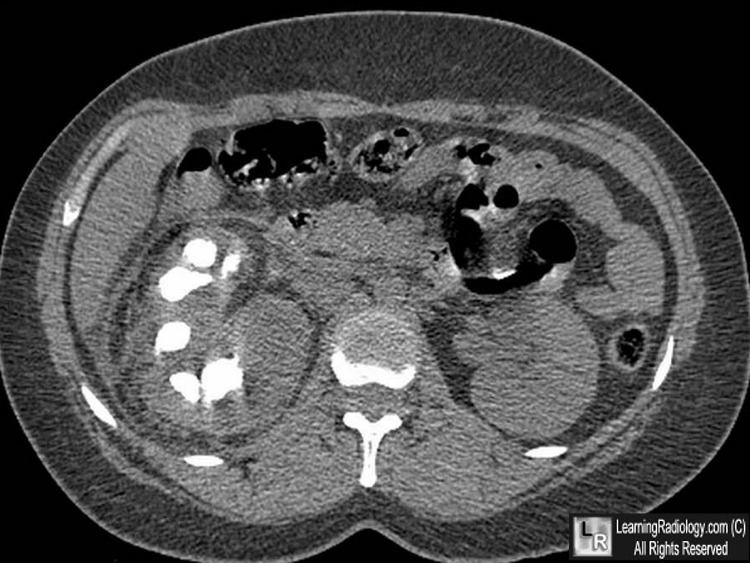

Grade III Renal Trauma

laceration >1 cm not involving the collecting system (no evidence of urine extravasation)

vascular injury or active bleeding confined within the perirenal fascia